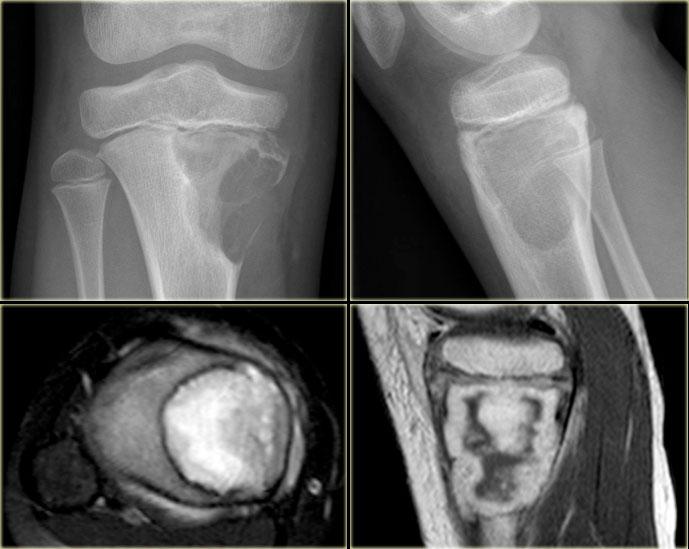

Hình ảnh bên trái của một u xơ sụn dạng nhầy (CMF).

Có một tổn thương tiêu xương lệch tâm ở vùng hành xương của đầu gần xương chày.

Ở phía trong có một bờ xơ cứng.

Ở phía ngoài có sự phá hủy vỏ xương đều đặn với lớp xương ngoại vi.

Hình ảnh MRI cũng cho thấy bờ xơ cứng với cường độ tín hiệu thấp.